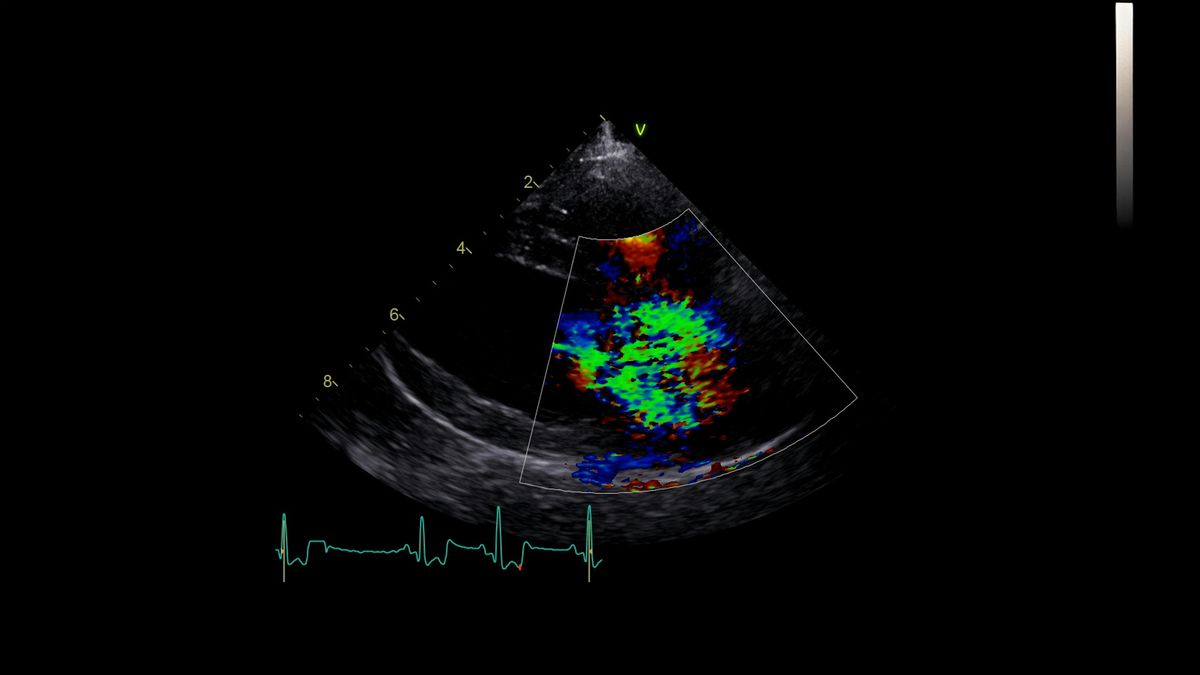

The day will begin with a warm welcome and an introductory echocardiography session, including a short talk followed by practical scanning, led by our cardiology team. After a refreshment break, participants will continue refining their echo skills in small, supportive groups.

💼 Topics: Echocardiography, surgery, imaging, and more